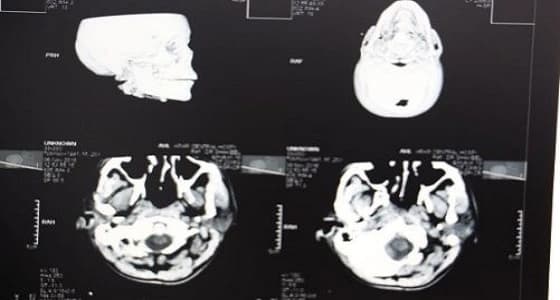

تمكّن فريق طبي بمستشفى عرعر المركزي من إنقاذ حياة مقيم إثر تعرضه لحالة دهس، حيث كان يعاني من إصابات متعددة انتفاخ واحتشاء نزفي شديد بالمخ ، كسر بالجمجمة والفك ، انحراف شديد للخط الناصف للمخ ، كسر بكامل القدم اليسرى.

وقام الفريق الطبي بقيادة استشاري جراحة المخ والأعصاب بإجراء عملية خزع جمجمة طارئ والاحتفاظ بجزء من عظم الجمجمة في جدار البطن، وذلك للسماح بتمدد أنسجة المخ خارج تجويف الجمجمة وتقليل الضغط داخل المخ حيث أثمرت نتائجها - بحمد الله -. وبعد استقرار حالة المريض تم إجراء العملية الثانية وهي تجميلية بالوجه للجهة المتضررة وبعد تحسن حالة المريض تم عمل العملية الجراحية الثالثة وإعادة تثبيت عظم الجمجمة في مكانه، وبعد أن تحسنت حالته الصحية تم السماح له بالخروج من المستشفى وهو بصحة جيدة ووضعه الصحي مستقر.